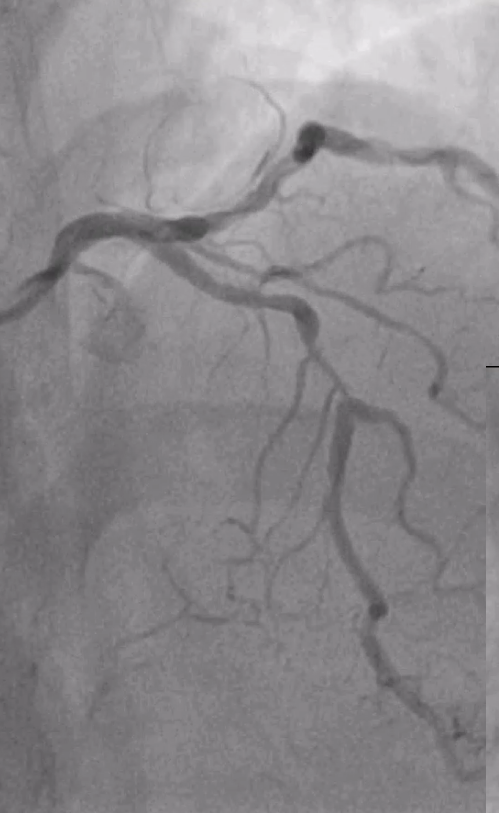

CAG S/O TRIPLE VESSEL DISEASE, WITH RCA CTO FILLING RETROGATELY. ADVICE CABG BUT PATIENT IS NOT WILLING FOR CABG

PTCA with Retrograde Rendezvous for Chronic Total Occlusion (CTO)An individual with a stubborn Chronic Total Occlusion (CTO) in the RCA (Right Coronary Artery) initially underwent a failed antegrade percutaneous transluminal coronary angioplasty (PTCA). Despite multiple wire attempts (e.g., CROSSIT 200, PILOT 150), the procedure was aborted due to a spiral dissection.A month later, a second attempt was made using a more advanced approach. The steps were as follows:Retrograde Access: The interventional team chose a retrograde approach, navigating a wire and microcatheter through collateral vessels to reach the RCA distal to the blockage.Antegrade Access: Simultaneously, an antegrade wire was advanced from the proximal end of the RCA to the blockage site.Rendezvous: The retrograde and antegrade wires were "kissed" at the site of the CTO. This crucial step, known as the rendezvous technique, allowed the antegrade wire to be precisely guided.Final Crossing: The antegrade wire was then advanced through the antegrade microcatheter, alongside the retrograde wire, finally penetrating the true lumen distal to the CTO.Revascularisation: Once the path was clear, the retrograde wire was removed. The RCA was then successfully revascularized with balloon dilations and the deployment of two stents.